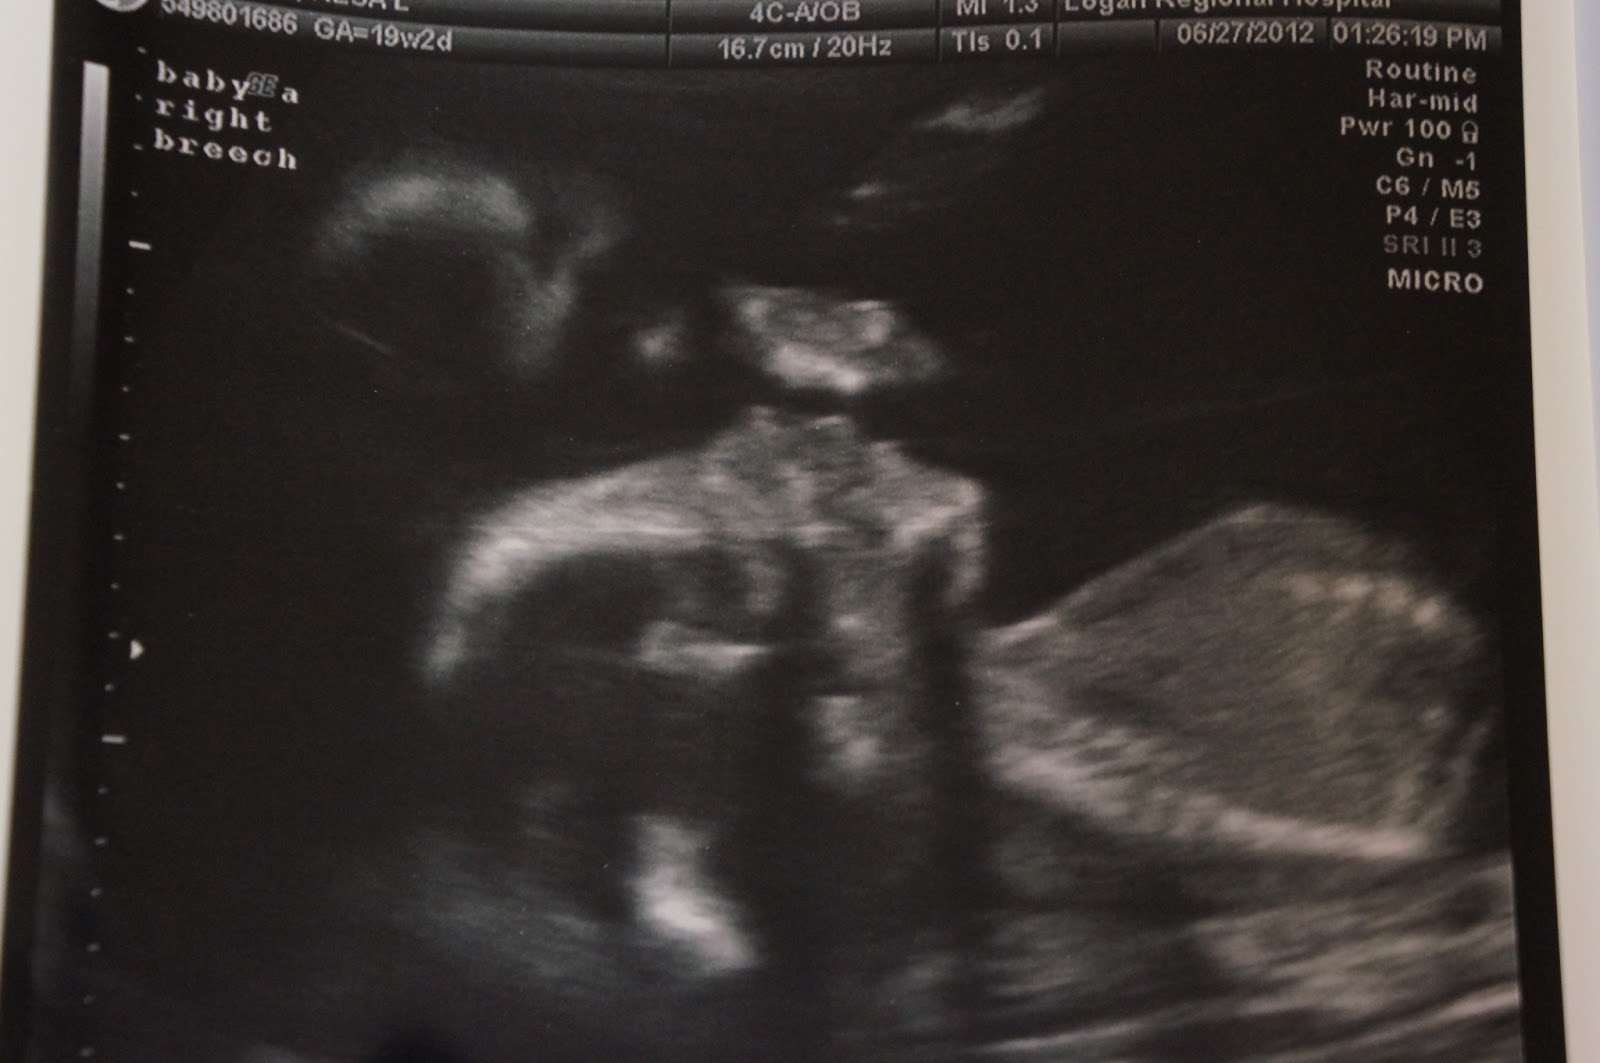

IDENTICAL twin BOYS!!! Yah, the news is still the same...and somehow, so is my reaction! Every time I tell anyone or I have someone ask me about it my heart starts racing and I think...IDENTICAL twin BOYS!! Because you know me, everything is CAPITALIZED when it's exciting and I'm slightly FREAKING OUT! :)

Oh that's right, because there are TWINS in that belly. IDENTICAL twin BOYS!! (Yep, still slightly freaking out at that news!) That's how it got so big. Two babies the lengths of large carrots. (Last week the e-mail said bananas, this week carrots...I think a banana sounds bigger personally.) Does that blow anybody else's mind? Cause mine sure is blown. I swear it wasn't too long ago they were only the length of an almond or an apple. Does time always go this fast with babies?